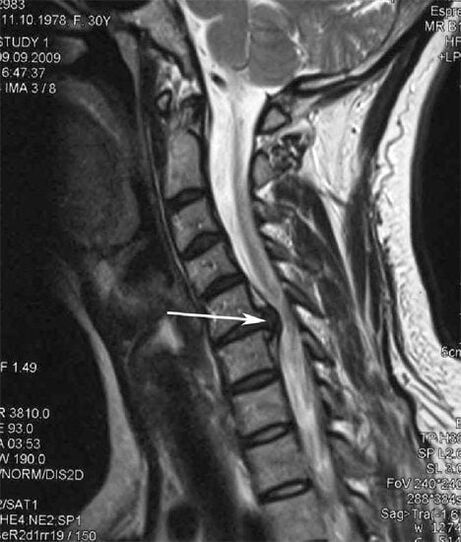

Im Frühstadium wird Osteochondrose mittels MRT erkannt. Anschließend kann die Pathologie durch Röntgen diagnostiziert werden. Auf Röntgenaufnahmen der Halswirbelsäule fallen eine Verringerung des Wirbelabstands, pathologische Veränderungen der Wirbelgelenke und eine Osteophytose auf.

Viele Menschen klagen darüber, dass sie ihren Hals nicht drehen können, weil sie starke Schmerzen haben, wenn sie plötzlich etwas Schweres heben. Dieses Phänomen deutet auf die Entstehung eines Bandscheibenvorfalls hin. Die Ursache für Schmerzen im Rücken, Nacken und in den oberen Extremitäten ist das Einklemmen einer der aus dem Rückenmark austretenden Nervenwurzeln.

| Zervikale Osteochondrose | Das Auftreten pathologischer Veränderungen in einem oder mehreren Bewegungssegmenten der Wirbelsäule. Beeinträchtigte Beweglichkeit der Wirbelsäule, Entwicklung myofaszialer Schmerzsyndrome und Einklemmen der Wirbelsäulenwurzeln | Schmerzen, Parästhesien und motorische Störungen im Halsbereich, die sich bis zum Hinterkopf und den oberen Gliedmaßen erstrecken. Erkennung charakteristischer Veränderungen der Wirbelsäule im MRT und Röntgen (Osteophyten, Verringerung des Wirbelabstands, Anzeichen einer Schädigung der Zwischenwirbelgelenke) |